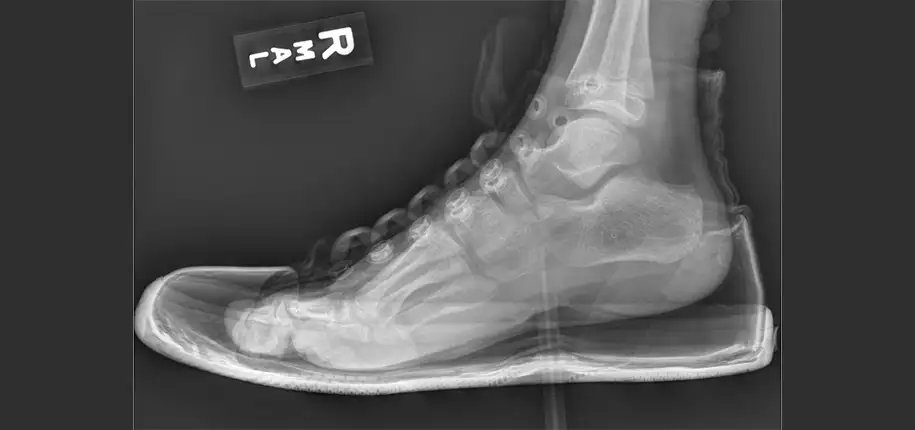

The phrase “watch your step” became very true in the case of a young boy who accidentally stepped on a pencil at school. An x-ray was obtained in order to precisely determine the depth of the pencil within the foot to help rule out associated injury to the foot, as well as to help plan for its removal. In most instances, when a patient comes to have a foot x-ray obtained, the patient’s shoes and socks are removed at the time of examination to aid in evaluation. However, in this case, it was decided for both the ease and quickness of diagnosis that the shoe would be left on in performing the x-ray. The phrase, “if the shoe fits, wear it” took on a whole new meaning. X-ray in this case not only helped to categorize the injury, determine the exact location of both the pencil and its lead within the patient’s foot aiding in its removal, but it also helped to provide an additional “diagnosis” of the patient’s popular brand of shoe. The shoe itself became a highlight instantly recognized by many of its fans as the Converse Chuck Taylor, proving that an x-ray can, in fact, see right through you and your shoe!